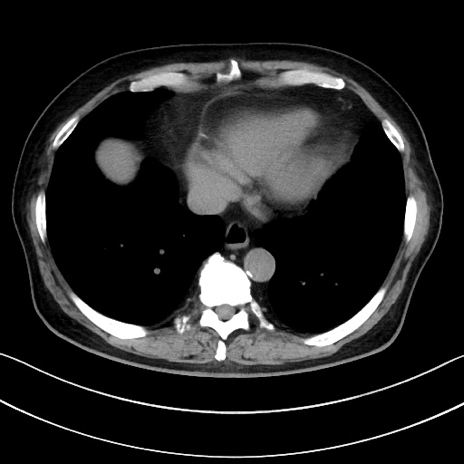

症例15(横断像)

【症例】70歳代男性

【主訴】腹痛

【現病歴】今朝から腹痛あり。全体的に痛い。特に左上の方。排ガスが今日はない。冷や汗が出る。

【既往歴】直腸癌術後

【身体所見】左側腹部〜上腹部に圧痛あり。腹膜刺激症状明らかなではない。軽度反跳痛。左下腹部に術後瘢痕あり。

【データ】WBC 7700、CRP 0.02